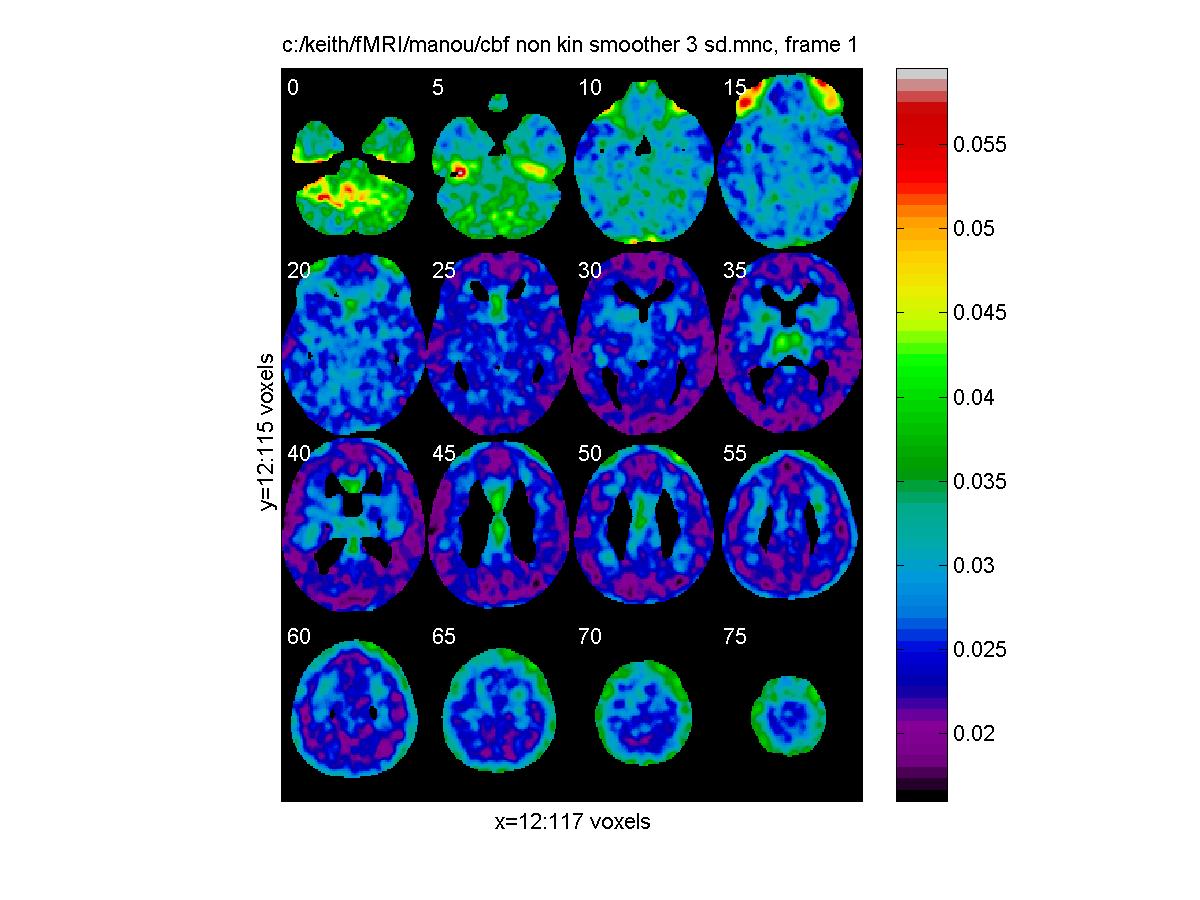

Standard error, in units of normalized cbf:

clf;

view_slices('c:/keith/fMRI/manou/cbf_non_kin_smoother_3_sd.mnc',mask,0.65,[0:5:79])

![[Click to enlarge image]](figs_pet_tn/fignormsd.jpg)